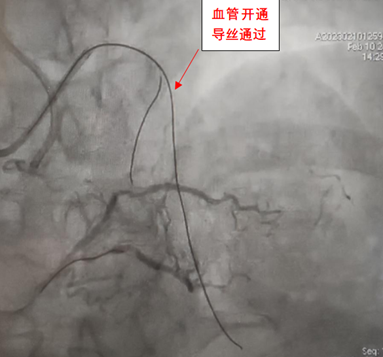

手术在洪浪教授的指导下进行,手术方案采用正向导丝技术、球囊拘禁策略保护第一对角支。经过多种特殊导丝的尝试,最终证实gaia 3导丝在血管真腔,植入2枚支架,手术总时间不到2小时。由于入路采用了左右桡动脉,做完手术立即就可以下床活动。术后患者对医护团队竖起大拇指:“找洪浪教授就是安心,真心为您们高超的医疗技术点赞,感谢您们的辛苦付出!”